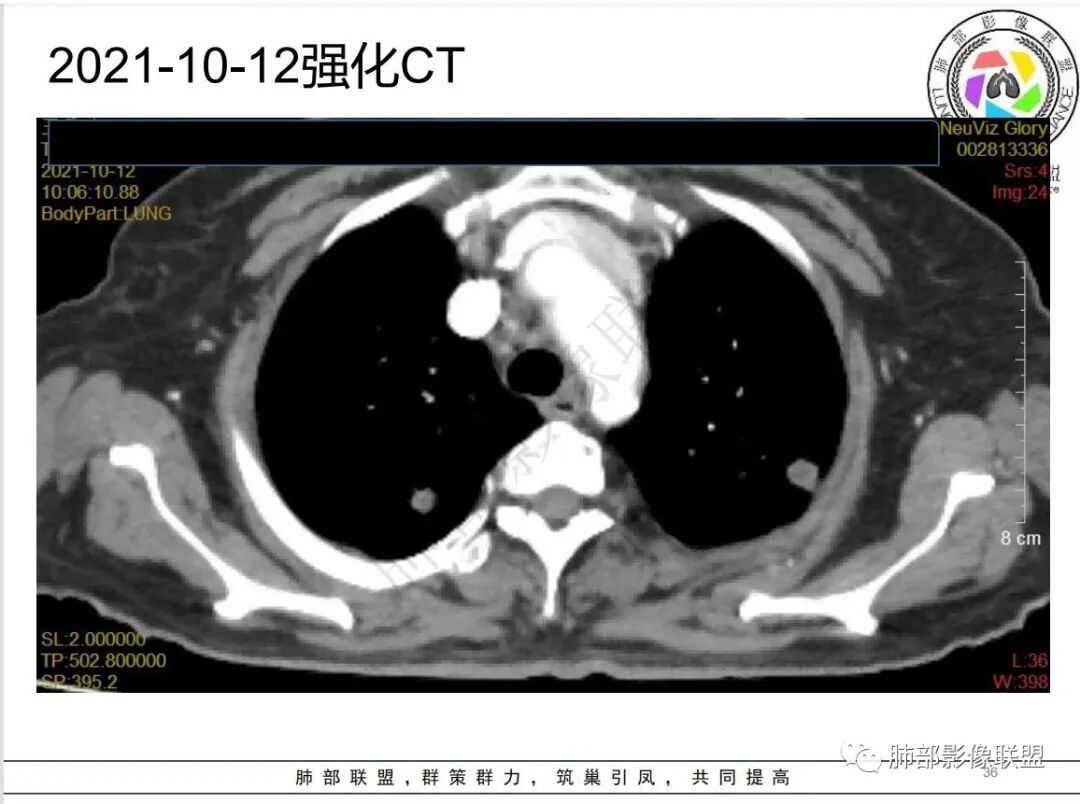

4.白血病化疗后,CT上出现多发结节,边缘可见晕征,病灶内可见多发坏死,右肺中叶肺动脉可见充盈缺损,右肺中叶可见融冰征,右肺中叶肺动脉侵犯栓塞伴右肺中叶肺梗死,可符合真菌感染。

血管侵袭性曲霉病是最常见的类型,其特征是真菌菌丝侵入和阻塞中小肺动脉,形成凝固性坏死、肺泡出血或出血性梗死。

6.肺曲霉病典型的CT表现是结节周围有磨玻璃样的晕征表现,或胸膜为宽基底的楔形实变。晕征表现为曲菌感染的肺结节伴梗死和凝固性坏死,周围有肺泡出血。最终可出现空泡征象,并可观察到中央坏死组织与周围肺实质分离形成空气新月征。

晕征已被认为是侵袭性曲菌病的早期征象之一。